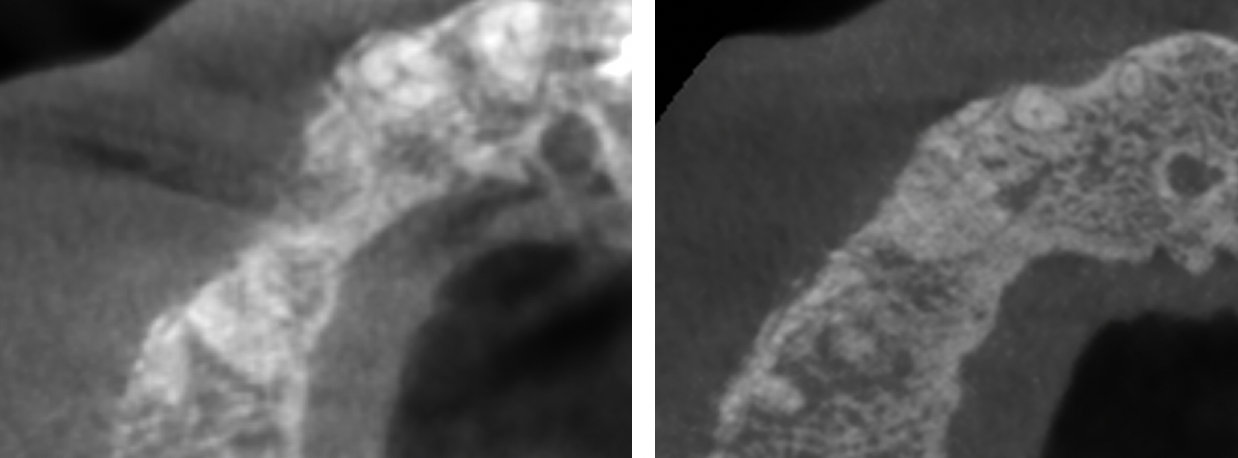

Dacă timpul scurs până la tratament este mai lung sau există procese patologice care afectează țesutul osos, atunci probabilitatea necesității unei reconstrucții crește. În acest sens există alte două scenarii. Dacă pierderea osoasă nu este mare, medicul poate să aplice implantul și să facă reconstrucția osoasă în același timp, urmând o perioadă de vindecare de 4-6 luni, după care va fi aplicată coroana dentară. Dacă pierderea osoasă este mare se impune în primul timp reconstrucția osoasă (Fig. 7.4.2), iar după 4-6 luni de vindecare aplicarea implantului urmată sau nu (în funcție de calitatea osoasă) de alte 4-6 luni de vindecare.

Figura 7.4.2 Imaginea radiologică a unui defect osos maxilar înainte și după reconstrucția osoasă